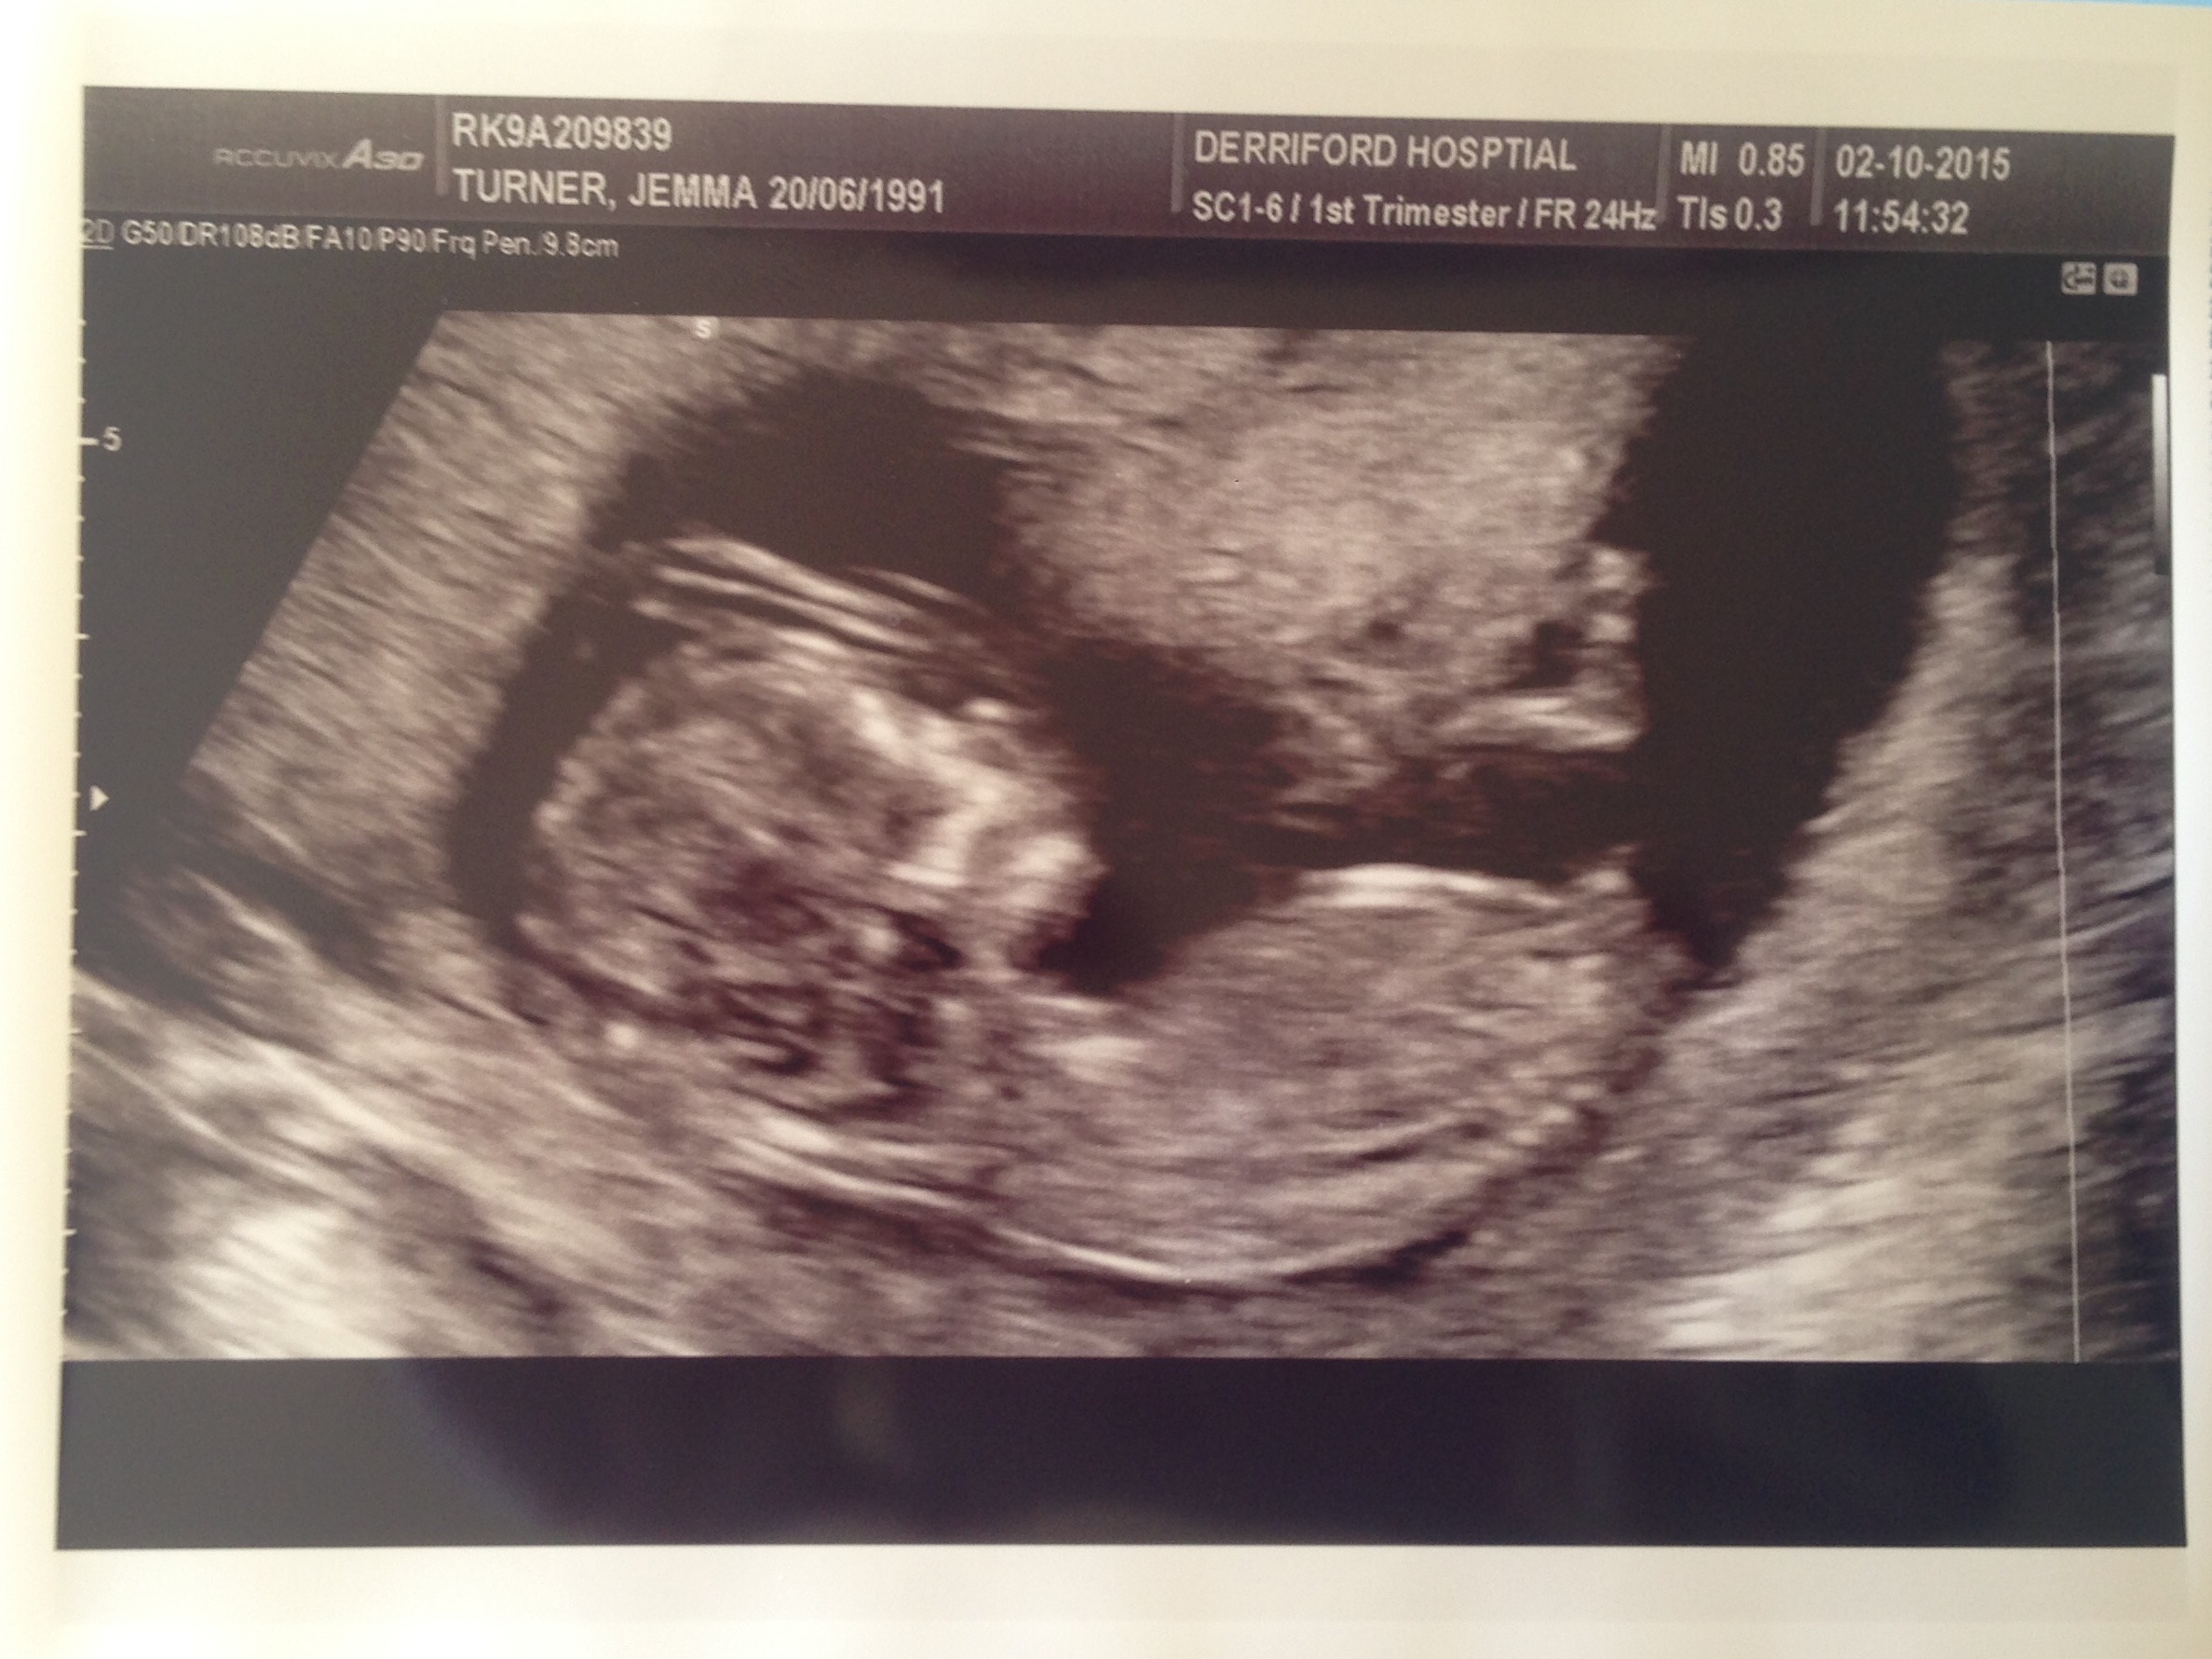

12+1 boy or girl?

Hi! This is my scan at 12+1, I am now 17+1 and find out on the 24th what babies gender is. Just for fun, would anyone like to guess please? Most people have guessed a certain gender (which I believe) but would love some fresh eyes and new guesses! Thanks :)Attachment 28306Attachment 28307

Thank you. I've been told boy but a few said girl because nub is parallel to the spine but also has something at the end of the nub lol slightly confusing

Totally a boy! Nowhere near parallel in my book lol. Almost vertical! Very cute <3